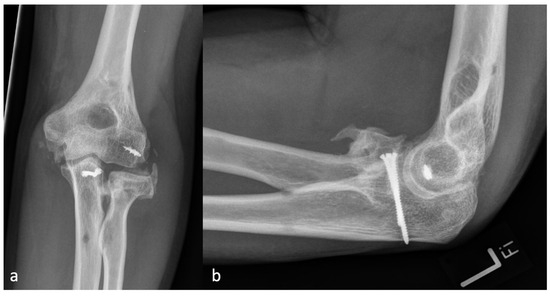

Figure 3.

(a) shows the AP and (b) shows the lateral X-ray with an anterior HO (23.4 mm) which is larger than the diameter of the radial head (19.2 mm) and represents an HO 2a.